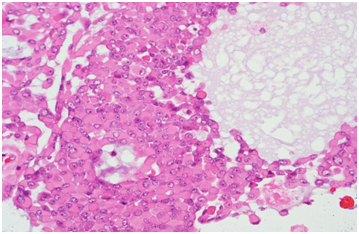

Microscopic examination showed well encapsulated tumor composed of sheets and islands of monomorphic round to polygonal cells with eccentrically placed plasmacytoid nuclei and abundant glassy eosinophilic cytoplasm lying in myxomatous stroma. No mitosis or necrosis seen. (Figure 5 & 6) Immunohistochemistry for Vimentin, CK, S100, CK7 were positive and the final diagnosis was Myoepithelioma-Plasmacytoid variety of minor salivary gland.

Figure 5 Histology of the tumor.